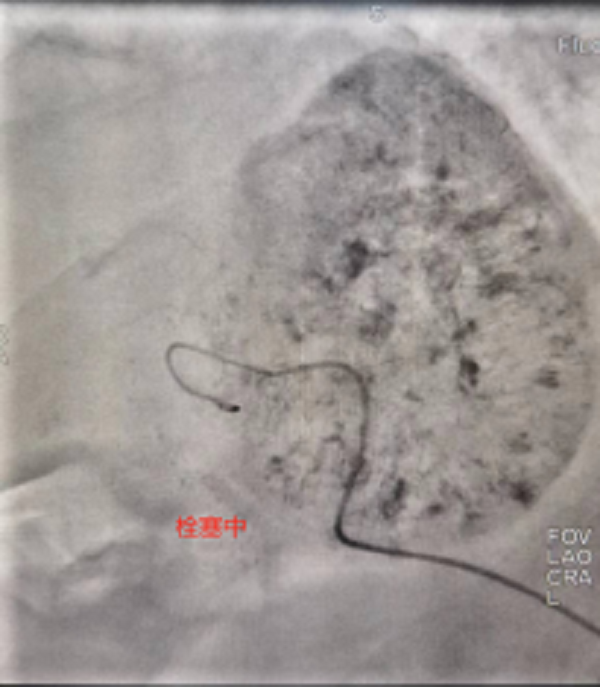

此次来院检查腹部增强CT提示:肝右叶占位性病变,考虑为原发性巨块肝癌,肿瘤大小达到60mmx84mm。患者之前已进行过结肠癌根治性右半结肠切除+胆囊切除术,病情复杂,身体虚弱,患者及家属强烈要求行微创介入治疗。经术前充分沟通及告知各种治疗方案的优缺点后,介入团队选择为患者行TACE介入微创治疗,后续将与靶向、免疫联合治疗达到肝癌的综合治疗。经过积极术前准备,普外科介入团队成功为患者实施了首例肝动脉化疗栓塞术,手术过程顺利,术后患者恢复良好,正在医院接受后续治疗。

肝动脉化疗栓塞术-TACE治疗是经皮穿刺动脉血管,用导管选择肝肿瘤靶血管后,经导管灌注化疗药,再用栓塞物质阻断肝肿瘤血供的治疗方法,是一种把肿瘤细胞“饿死”的介入治疗技术。